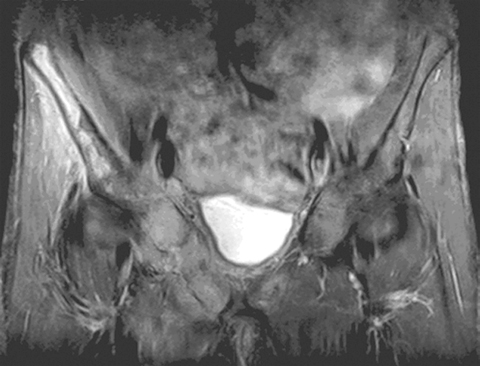

MRI helped in making the diagnosis and delineating the extent of the muscle involvement in all patients, as (see Box 2) the high signal intensity of the pathological process (prolonged T2) can be easily distinguished from the relatively low signal intensity of normal muscle (shortened T2). The superiority of MRI for differentiating pyomyositis from other pathological processes, outlining the extent of involvement and localising fluid collections, has been previously reported.8 The ability of MRI to obtain multiplanar contiguous sections provides excellent anatomical detail of each muscle group and precisely locates the site of disease. MRI scans in 43 cases of pyomyositis found that hyperintense signals on T2-weighted images were detected in all patients.18 A hyperintense rim on unenhanced T1-weighted images and peripheral enhancement after gadolinium injection was useful for identifying the number, size and location of soft tissue abscesses.18